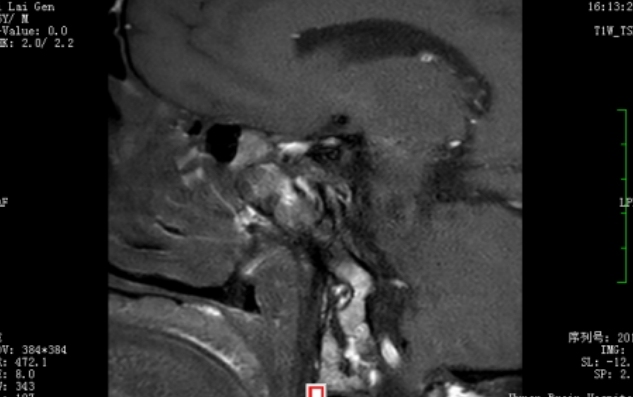

术后MRI检查